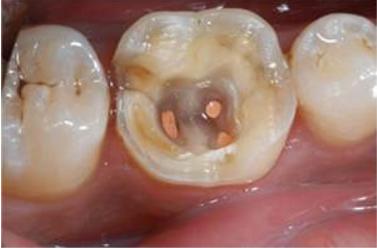

牙齿的结构比较特殊,它的四周是硬的牙釉质和牙本质,中间是牙髓腔,牙髓腔在牙齿发生感染的时候往往会成为细菌传染的通道。

进食后口腔的残渣会在口腔内产生细菌,口腔的细菌也就是通过牙齿髓腔这个通道,细菌通过根管后会在牙根周围的骨组织和牙周膜它们之间循环往复的交互,从而引起牙髓组织的感染。

根管治疗就是通过把这染上细菌的牙髓剔除干净,用材料进行堵上,再用消毒药隔绝牙髓腔这个细菌传染的通道,从而保护牙齿,使它能够继续使用。

第二,根据具体情况选择实施麻醉与否,尽量让根管治疗在无痛的情况下进行操作,钻开牙齿取出腐败坏死的牙体组织,

第三:打开牙髓腔,取出被感染的牙髓;